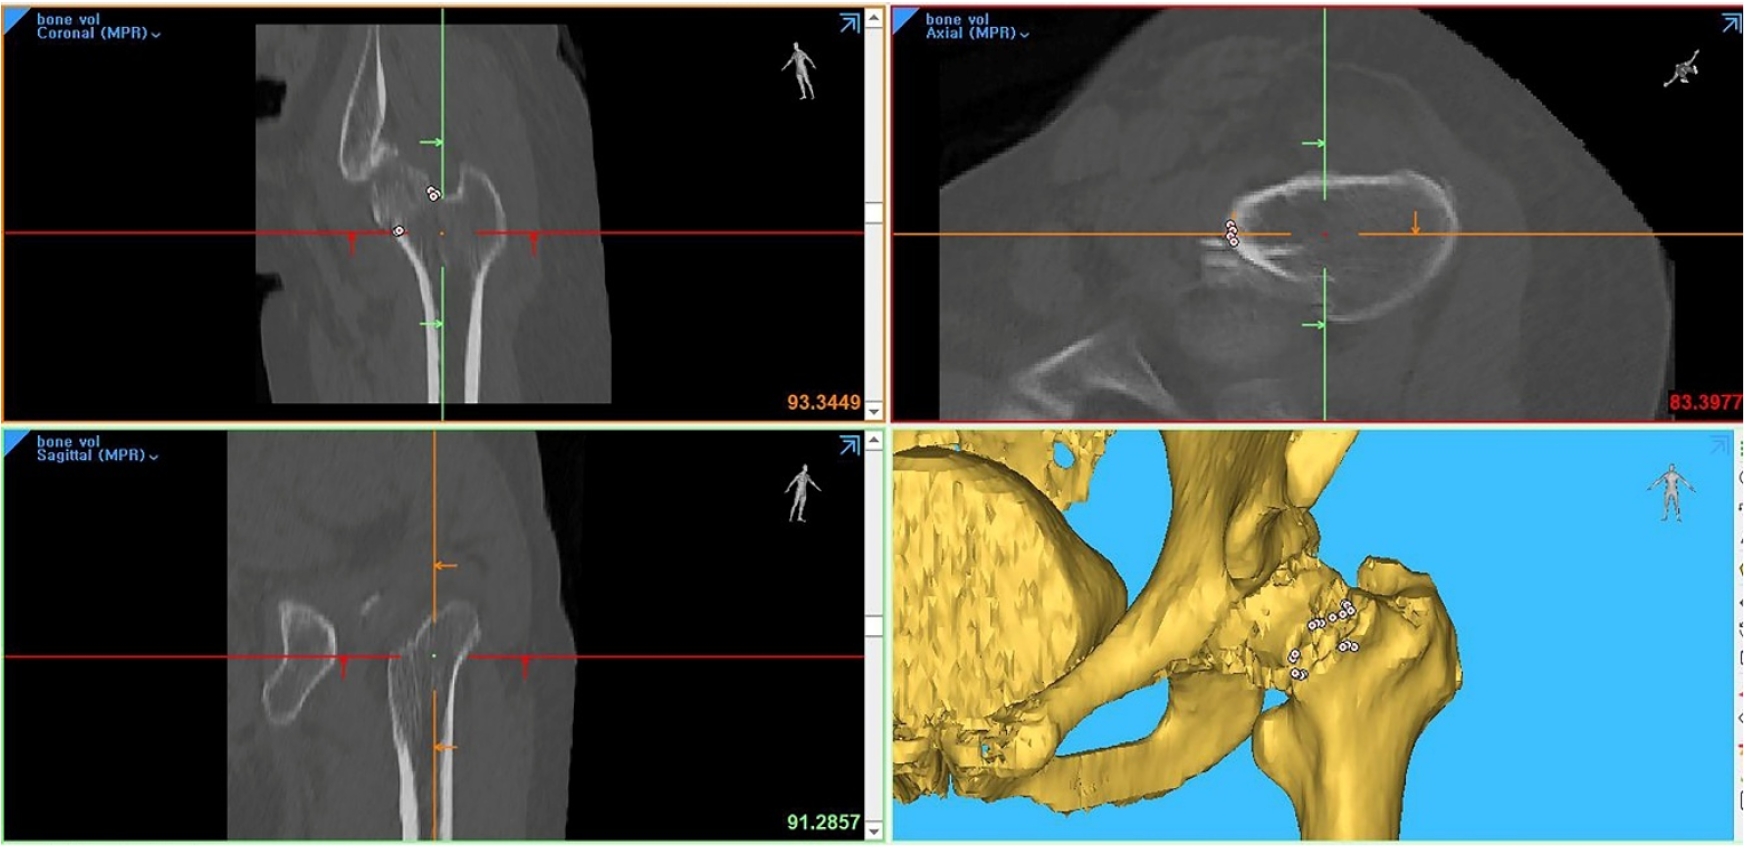

Although Pauwels biomechanical classification is in use nowadays, practical measurement of coronal verticality had lower reliability in preoperative radiographs due to projection errors and leg deformity during radiographic examination [11,16,17]. Considering that femoral neck fractures in non-older adults inevitably have significant displacement and comminution of fracture site, the conventional method to measure the PA is technically difficult in practice. Thus, we performed verticality measurements in multiple sites based on a previous study [11]. Through this imaging study, we would introduce how to apply Pauwels classification in practice after eliminating projection error of comminuted neck fracture in non-older adults. By using the software to allow free 360° rotations with magnification in any plane, this study has several interesting and practical findings. First, among six coronal images, the centerline image had the highest value of coronal PA. The coronal PA of the 1st central image was a mean value of 55.43°±13.79° and the 1st posterior images, mean value of 51.44°±11.13 (P=0.003). Second, CT scanning planes along the centerline of the femoral neck in coronal and axial planes could be used to measure the maximal fracture verticality without specialized software or equipment (Fig. 6). Third, fractures of the linear type in the coronal plane and trochanteric type in the axial type had higher verticality than other types. Thus, they were classified into the high verticality group.

Fig. 6.

A 38-year-old male patient presented with hip pain following a 3 m fall. (A) The initial plain radiograph revealed a femoral neck fracture. (B, C) The computed tomography (CT) plane parallel to the femoral neck centerline identified a convex fracture with a Pauwels angle of 45.1° in the coronal plane. (D, E) Reorientation of the CT plane along the femoral neck demonstrated a cephalad-type fracture with an axial verticality of 75.8° in the axial plane.

jmt-2025-00038f6.jpg

Fig. 6. A 38-year-old male patient presented with hip pain following a 3 m fall. (A) The initial plain radiograph revealed a femoral neck fracture. (B, C) The computed tomography (CT) plane parallel to the femoral neck centerline identified a convex fracture with a Pauwels angle of 45.1° in the coronal plane. (D, E) Reorientation of the CT plane along the femoral neck demonstrated a cephalad-type fracture with an axial verticality of 75.8° in the axial plane.